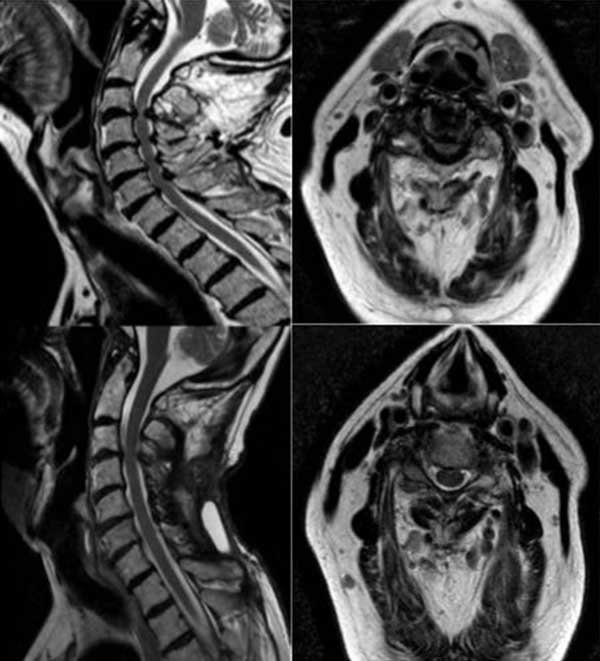

Caso 2

Paciente masculino de 72 años, con tetraparesia severa de instauración aguda secundario a latigazo cervical. Al examen físico: tetraparesia severa asociado a hipoestesia en 4 miembros a predominio de miembros inferiores y globo vesical. Nurick prequirúrgico de 5. En RM se observó una disminución del diámetro del canal cervical asociado a signos de edema medular (Figuras 8 y 9). Se propuso efectuar una laminoplastia entre los niveles C3-C7. No se evidenciaron cambios en la escala de Nurick.

Figura 8. Imágenes en corte sagital y axial de RM T2 cervical prequirúrgica (imagen superior izquierda y derecha) donde se observan múltiples osteofitos posteriores e hipertrofia facetaria con edema medular asociada y estrechamiento del canal espinal cervical a nivel C3-C7. Las imágenes posquirúrgicas (imagen inferior izquierda y derecha) evidencian la ampliación del canal espinal y descompresión medular.